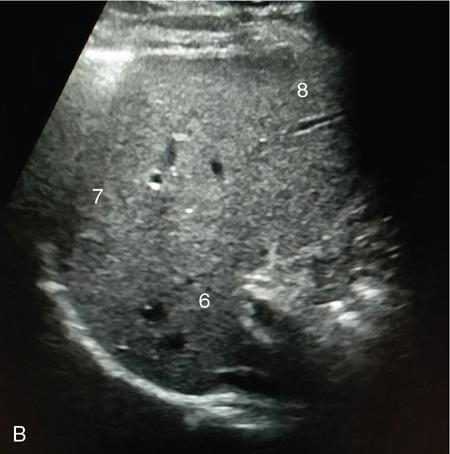

Samarjit Ghuman, Seema Sud, Deeksha Rastogi, Swapnil Sheth, T.B.S. Buxi PLAIN RADIOGRAPHY FOR HEPATOBILIARY IMAGING The diagnostic imaging techniques for hepatobiliary imaging can be intimidating with many techniques/modalities providing the information desired. The job of the diagnostic radiologist includes being familiar with the available choices and pick the ‘best fit’ keeping in mind the pros and cons of each modality, which includes plain X rays, Contrast studies using plain X rays and fluoroscopy, Ultrasound includiojng Doppler and Ultrasound elsastography, CT including multiphase CT and MRI and MRI elastography. Understanding the strengths and weaknesses of every modality as well as the ability to tailor each study individually will help to optimise patient cares. The abdominal radiograph is performed almost exclusively in the supine position and in the AP (anteroposterior) projection. In case of acute abdomen, an erect chest radiograph should also be performed to look for free air under the diaphragm. The standard abdominal radiograph should extend from the diaphragm to the inferior pubic rami, and includes the lateral abdominal wall musculature. Routinely no preparation is required for abdomen radiograph done for hepatobiliary imaging. The radiograph has limited soft-tissue contrast, however, the liver being the largest intra-abdominal organ, casts a perceptible shadow. The margins of the liver can indirectly be seen by outline of adjacent organs like lung, hemidiaphragm, pro-peritoneal fat line, kidney and gas shadows of stomach/colon. The right lobe is seen better than the left lobe of liver. The following pathologies may be visualized on the plain radiograph of the liver. Liver enlargement Liver mass Calcification Increased radiodensity of the liver Decreased radiodensity of the liver An ultrasound is the first line investigation; however, a radiograph may be done for routine evaluation of abdominal pain. The following pathologies may be seen on plain radiograph of the biliary tree. Calculi and Calcifications Gas ULTRASOUND OF HEPATOBILIARY SYSTEM Ultrasonography (USG) is the initial imaging modality of choice for scanning hepatobiliary system. USG is accurate and has high sensitivity and specificity in diagnosing biliary pathologies. Table 9.1.1 shows indications of ultrasound in hepatobiliary system. The real-time nature of ultrasound lends itself to demonstrate mobility of calculi and sludge and the sonographic Murphy sign can easily be elicited during scanning. The main disadvantage is operator dependence, patient’s body habitus, presence of gas which can obscure the visualization of organs, overlying bandages in a postoperative patient and incomplete evaluation in a nonfasting state. USG of upper abdomen should be done after 6–8 hours of overnight fasting. Milk and fatty food should be avoided as they cause contraction of the GB and may cause the GB walls to appear thickened. History of previous surgery, especially cholecystectomy should be elicited. The patient may be positioned in supine or left lateral decubitus position. The GB can be scanned from a high/lateral view, looking through the ribs in supine position or through a sub-costal view in left lateral decubitus position. Position of patient may be changed to demonstrate mobility of structures. The GB is an anechoic structure which is located in the GB fossa along the posterior and inferior aspect of the liver. It has a fundus, body and a neck. It should always be examined in at least two planes (Fig. 9.1.6A and B). The wall of the normal GB should measure 3 mm or less and pathological GB wall thickening can be due to cholecystitis or a neoplastic aetiology. Calculi appear as mobile hyperechoic foci, with distal acoustic shadowing. Other pathologies include polyps and sludge which can be differentiated on the basis of their mobility. The CBD measures less than 6 mm in diameter with increase in the diameter with patient’s age and after cholecystectomy. The CBD is usually scanned in an oblique subcostal plane with the patient in the left decubitus position (Fig. 9.1.7). Dilatation of the intrahepatic biliary radicles is readily assessed with USG and normal intrahepatic biliary radicles are usually not appreciated on USG. Ultrasound of the liver, broadly, is done to assess the size, surface (smooth, coarse or lobulated) parenchymal echogenicity (increased or decreased) vascularity and for presence and evaluation of intrahepatic masses or fluid collections. The liver is divided into right and left lobes by plane of middle hepatic vein which passes through GB fossa and notch of IVC (Cantlie Line). Couinauds classification is the most commonly used system for liver segmental anatomy and described liver into eight functional segments. It is based on distribution of portal and hepatic veins. Every segment has its branch from portal vein, hepatic artery and bile duct (Fig. 9.1.8). Curvilinear transducer (3–5 MHz) is used for routine examination of liver and GB (Fig. 9.1.9). A high-frequency linear transducer (9–11 MHz) (Fig. 9.1.10) can be used to look for subtle irregularity of the liver surface for early Cirrhosis and fine details of GB wall. The liver is scanned in deep inspiration, which causes inferior movement of liver, so that superior borders of the liver are well visualized. Supine position is used for the size of the liver. The measurement is made in sagittal mid clavicular position on right side, in craniocaudal dimension. It is taken from diaphragm to the lower end of the liver. It should be <16 cm and varies with age and sex. The liver is divided into four vertical sectors by three hepatic veins and plane of bifurcation of portal vein divides these 4 sectors in to 8 segments. The right hepatic vein creates vertical plane in the right lobe separating segments V and VIII (anterior) from VI and VII (posterior). The portal vein bifurcation creates a transverse plane and divides these segments into superior (VII, VIII) and inferior segments (V, VI). The left hepatic vein divides the left lobe into medial (IVa, IVb) and lateral sectors (II, III). The left portal vein divides left lobe into superior (Iva, II) and inferior segments (III, IVb). The middle hepatic vein separates medial segments of left lobe (IVa, IVb) from anterior segments of right lobe (V, VIII). Ligamentum teres separates segment III from IVb. Ligamentum venosum separates segment I from IV and II. Cystic duct is an anechoic tubular structure which connects neck of the GB to the extrahepatic biliary tree. In long axis view of GB, the neck of the GB is related to main lobar fissure which appears as a linear echogenic line which runs obliquely between neck of GB and right portal vein. In the right oblique sub coastal view CBD is seen anterior and parallel to portal vein. A series of standardized sections or views may be obtained for liver scanning. Transverse Subcostal View: In this view the probe is angled cephalic and placed transversely under the ribs on the right side and portions both lobes of the liver can be seen (Fig. 9.1.11). Mid Transverse View (Fig. 9.1.12) in this transducer is kept in transverse plane in the midline below the xiphisternum. It visualises the liver in an inferior to superior transverse oblique plane and portions of both lobes of liver can be seen along with right and left portal veins. This view is obtained by angling the transducer superiorly toward the hepatic venous confluence. In this view, we can see the three hepatic veins joining the IVC. Right Parasagittal View for Both Right Lobe and Kidney: This view allows assessment of inferior right lobe of liver. It also allows assessment of relative echogenicity of liver and renal cortex as both are seen together in the same image. Normal liver parenchymal echogenicity is greater than renal cortex and less that renal medulla (Fig. 9.1.14). Parasagittal Right MidClavicular View: In this transducer is kept in sagittal plane in right midclavicular line, and oriented supero-inferiorly. This is the standard view for assessing craniocaudal span of liver (Fig. 9.1.15). Parasagittal View for the Left Lobe: For evaluation of left lobe of liver and lateral segments (2 and 3) (Fig. 9.1.16). This view is obtained along the direction of the main portal vein. CEUS of the liver is done to evaluate Focal Liver Lesions and complements traditional B mode ultrasound and Doppler study. It is a simple, accurate and cost-effective tool complimenting indeterminate CT and MRI findings or for characterization of lesions in patients who cannot receive CT/MRI contrast and can be used in patients with compromised renal function, with minuscule risk of side effects. As CEUS is real-time, microvasculature can be studied along with tissue perfusion kinetics. Indications and uses of CEUS: Contrast agents and technique: Interpretation: Contrast-enhanced ultrasound of a hepatic hemangioma in different phases (Fig. 9.1.19). Limitations of CEUS: Liver elastography is a noninvasive method for diagnosing liver fibrosis. Liver fibrosis is induced by chronic liver disease leading to cirrhosis and liver cancer. Liver biopsy is the gold standard for diagnosing the degree of fibrosis and for staging but it is an invasive method. Elastography helps in analysing the elasticity or the stiffness of the tissue. A stiffer liver tissue indicates fibrosis or chronic liver disease. ARFI is based on the principle of measuring Shear wave velocity. Short duration acoustic pulses which are generated in the tissue and these give rise to shear waves which travel, perpendicular to the ultrasound beam. These shear waves cause tissue displacement followed by recovery. This displacement and recovery depend on tissue stiffness. To monitor these shear waves US beams of low intensity are emitted continuously parallel to the main beam along with the push pulses, and these beams can gather data regarding the tissue stiffness. The shear waves cause tissue displacement and this tissue then recovers from the impulse. From this data the degree of tissue stiffness can be obtained which is displayed either as a map or quantitatively where tissue elasticity is expressed as shear wave velocity measured in meters per second. F0, normal; F1, enlarged fibrotic portal tract; F2, periportal/initial porto-portal septa with intact architecture; F3, architectural distortion with no obvious cirrhosis; F4, cirrhosis. It is also known as Transient Elastography (TE) and works on the similar principle as ARFI, the difference being that B mode ultrasound image is not produced. DOPPLER OF PORTAL VEIN The portal vein divides at the portahepatis into right and left branches. The right portal vein divides into anterior and posterior branches, and the left portal vein divides into medial and lateral branches. Portal vein shows a continuous, forward low-velocity flow (15–28 cm/s) on colour Doppler scanning. The flow is hepatopetal, that is, towards liver and is red in colour as it is flowing towards the transducer. It has an undulating pattern and shows respiratory variation with increase flow in inspiration. It may reflect cardiac variation and shows postprandial increase calibre and flow in healthy individuals. Normal Doppler waveform of portal vein (Fig. 9.1.22). Portal hypertension can be defined as elevated pressure within the portal venous system resulting in impaired blood flow through the liver. INTRAOPERATIVE PANCREATIC AND HEPATIC ULTRASOUND Intraoperative ultrasonography of the pancreas was first described in 1980 by Lane and Glazer. It is an important technique for guidance of both open and laparoscopic surgical procedures of the pancreas. As the transducer is in direct contact with the organ of interest, with no interference with air of adjacent soft tissue, it provides good resolution. It is considered superior to CT and MRI in assessing the intraoperative tumour resectability and vascular invasion and guiding resection. Indications and uses For intraoperative US during open surgical procedures, a high-frequency linear-array transducer or the hockey stick transducer (Fig. 9.1.23) are used which create high-resolution detail of the exposed pancreas. The side-fire curved linear-array transducer is effective for obtaining a wider view of the pancreas and its surrounding structures and for scanning the liver. Intraoperative hepatic ultrasound gives the real-time visualization of the hepatic anatomy and aid for surgical planning and making decision during surgery. Indications and uses Transducer and technique Limitations MULTIDETECTOR CT OF THE HEPATOBILIARY SYSTEM AND CHOLANGIOGRAPHY The cross-sectional plane of the patient is denoted as the x/y plane. The plane along which the table moves is the ‘z’ plane. Multidetector CT denotes more than one detector along the Z-axis, with the latest machines having up to 320 and now even 640 rows of detectors. This provides CT with very fast, high resolution, isotropic images which can be reconstructed in any plane or even curved planes. MDCT scanners can comfortably scan the entire abdomen in 10 seconds or less, thereby allowing visualization of different phases of contrast enhancement. Contrast Media (CM) after administration gets distributed from the intravascular compartment into the interstitial spaces. Intravascular arterial enhancement (for angiography) and parenchymal enhancement have different kinetics. Parenchymal enhancement is directly proportional to total iodine dose being administered and inversely proportional to weight, which is a marker of extracellular volume into which contrast redistributes. Rate of iodine administration has no effect on degree of parenchymal enhancement. As a general rule approx. 500–600 mg of iodine/kg body weight achieves adequate hepatic parenchymal enhancement. For a 60 kg adult, this translates into approx. 100–120 mL of contrast containing 300 mg of iodine per mL. Intravascular or arterial enhancement is controlled by rate at which iodine is administered (flow rate and iodine concentration of CM) iodine flux and duration for which contrast is administered longer injection also leads to better overall arterial opacification due to recirculation effects. This principle is made use of while performing abdominal CT Angiography. Higher iodine delivery rate per unit time using a higher iodine concentration contrast medium also improves conspicuity of vessels and hypervascular lesions such as HCC. For identical parameters, difference in arterial enhancement between patients is dependent on cardiac output with enhancement being inversely proportional to cardiac output. For optimal imaging and enhancement, in multiphase imaging and angiographic studies, contrast material administration and parenchymal or vascular enhancement must be synchronized with CT data acquisition. The two main methods are: Test bolus technique: A test dose of contrast is given and the time to peak enhancement is measured in a ROI placed in a target vessel this information can be used to tailor CT acquisition. Automated bolus Triggering: ROI is placed in target vessel (usually aorta at level of diaphragm) on a plain image. While CM is injected, a series of low dose scans is obtained through the ROI. When the density of contrast reaches a predefined threshold (e.g. 150 HU), at time ‘t’ the scan is automatically triggered. The trigger delay after time ‘t’ is a minimum of 2 sec, and can be programmed to any value. Bolus tracking is nowadays the method of choice for planning contrast medium administration and this technique provides more homogenous opacification. Saline chase is recommended in all multiphase protocols. Significant amount of contrast may be present in the peripheral veins after injection of IV contrast and use of saline chaser leads to better vascular enhancement and lower overall contrast dose (Fig. 9.1.24). Using the above, a standard sequence of acquisitions and contrast enhancement techniques can be tailored to the pathology and organ of interest and pre-programmed into the scanner menu, which includes kVp, mAs, pitch, rotation time, slice thickness etc. This is known as a scan protocol. However, these can be modified as necessary. For example, rotation time can be shortened and pitch can be increased for breathless patients to reduce scan times (Table 9.1.4). Multidetector CT is the workhorse of hepatobiliary imaging. It plays a major role in imaging congenital, traumatic, infective, neoplastic and vascular pathologies of the hepatobiliary system. Scans can be obtained with or without intravenous (IV) iodinated contrast material administration. Multidetector CT scanners are capable of imaging multiple phases at different points of time following injection of contrast and provide dynamic imaging due to fast scan times and rapid coverage of the abdomen. Indications for liver imaging include, but are not limited to: Unenhanced Scan: Hepatic fat estimation, radio opaque biliary calculi. Single Phase Scans: Liver abscess, polytrauma, follow up of known oncologic or benign lesions, abdominal pain, suspected cholecystitis. Multiphase Studies: Evaluation of hepatic masses, imaging in cirrhosis, imaging for resectability, liver donor evaluation, malignancy of GB, hepatic venous outflow obstruction etc. CT Angiography of Hepatic Vessels: Trauma, vasculitis, post-operative bleeding and as a part of multiphase studies. Depending on the indication, scanning protocols can be tailored to highlight the suspected pathology and provide relevant answers for further management (Table 9.1.5). The liver has a dual blood supply, most of which is derived from the portal vein. After injection of contrast, until the portal vein provides recirculated contrast material filled blood to enhance the hepatic parenchyma, the hepatic parenchymal enhancement is relatively poor and dependent only on the hepatic artery. The hepatic arterial phase can be divided into an early arterial phase without any portal opacification, a late arterial or portal inflow phase in which there is some portal vein opacification. This is followed by a portal venous phase in which portal and hepatic veins are enhanced (also called the hepatic venous phase in some articles). In addition, an unenhanced/plain scan and an equilibrium phase can also be acquired. Tumour conspicuity of hypervascular lesions was found to be best on the late arterial or portal inflow phase (Fig. 9.1.25). The early arterial phase is seen up to 10 seconds after trigger, and provides ‘angiographic’ images of hepatic arterial anatomy. This phase is used to provide details regarding arterial anatomy and morphology. Later arterial phase 18–23 seconds, portal venous phase 60–70 seconds and equilibrium phase 180 seconds are obtained after trigger. Equilibrium phase images have been shown to increase detection of hepatocellular carcinoma in cirrhotic patients. The portal venous phase is the standard phase for routine chest/abdomen survey and follow up of hepatic abscesses and hypovascular metastases. Single Phase Scan Protocol: Oncologic follow-up, Liver Abscess – For routine single-phase CT, contrast as per body weight can be injected over 40 seconds and scanning can be done after an empiric delay of 70 seconds from the beginning of injection. This protocol provides good parenchymal enhancement and portal and hepatic vein visualization. Plain scan is optional. Dual-Phase Scan Protocol: Hepatic evaluation in patients with malignancies known to have hypervascular metastases – Neuroendocrine tumours, renal cell carcinoma, thyroid carcinoma, (.) melanoma etc. Late arterial Phase 20–22 seconds and Portal venous phase at 60–70. Plain scan optional. Hepatic Resection Protocol: For patients with known hepatic mass being evaluated for resection. Early arterial phase provides pure arterial or angiographic images. It is obtained at 8–10 seconds post trigger followed by portal venous phase at 60–70 seconds. This is required for arterial and venous anatomy and volumetric evaluation if required. Plain scan is not required. In case a hepatic mass needs characterization as well as resectability planning, late arterial and equilibrium scans may also be done. Indications for angiography are further discussed in the section on angiography. The same biphasic protocol using angiography or arterial phase images is used in patients with trauma suspected to have pseudoaneurysms, hepatic artery thrombosis or dissection in transplant recipients, evaluation of living donors and in patients in whom an angiographic ‘road map’ is required prior to intervention. Triphasic or 4 phase scan Protocol: Standard of care for patients with cirrhosis being evaluated for Hepatocellular carcinoma and for patients being evaluated for hepatic mass of uncertain aetiology. Late arterial phase scan: 20–22 seconds, Portal venous scan at 60–70 seconds and Equilibrium scan at 180 seconds. Plains scans are optional. Our institutional practice is to always do plain scans in patients who have undergone hepatic intervention. Plain scans also help to visualize siderotic and steatotic nodules. A further delayed scan is suggested by some authors at 10–15 minutes for characterization of hepatic masses of uncertain provenance. This is particularly useful in cholangiocarcinoma (Table 9.1.6).

Hepatic anatomy on ultrasound